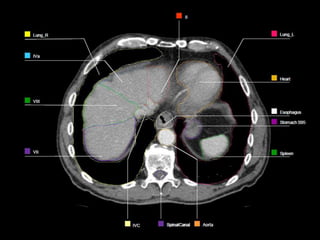

OARs

 Liver

 Kidney

 Stomach

 Spinal Cord

 Heart

 Duodenum

 Small Bowel

 Lungs